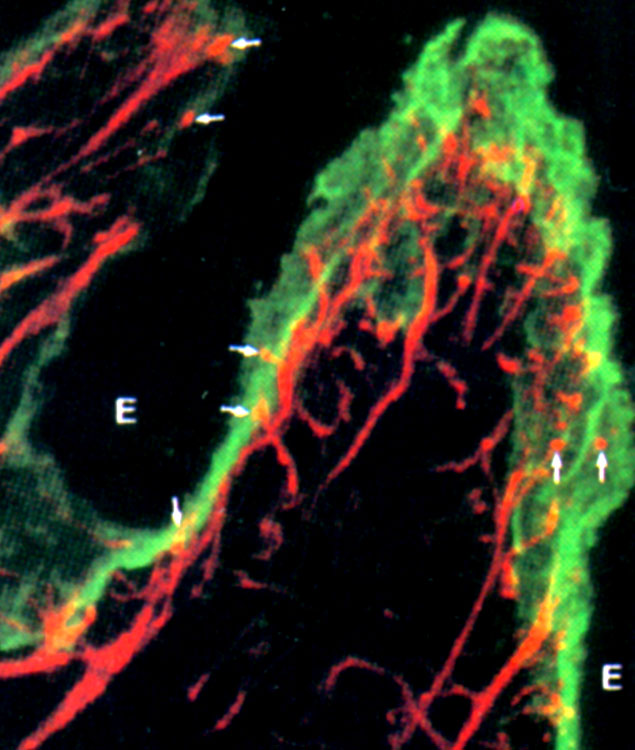

Neben den klassischen histologischen Färbungen werden wir Histochemie (Ausnutzung der lokalen Enzymaktivität) und Immunhistochemie (Nachweis und Lokalisation von Antigenen mittels Antikörpern) vertiefen.